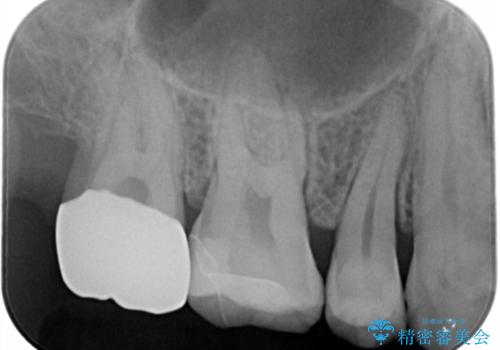

- 一番奥の銀の詰め物を白くしたいとのことで来院。

セラミックの詰め物のやりかえだと範囲が多く、割れてしまうリスクがあります。

そのため、割れるリスクが少ない詰め物ではなく、被せ物による治療(ジルコニアクラウン)を行いました。

また、隣の歯も白い樹脂の下が虫歯になっており、セラミックの詰め物(e-maxインレー)による修復をしました。

銀の詰め物のまま放置すると、歯との隙間から細菌が入り

虫歯の再発リスクが高まります。